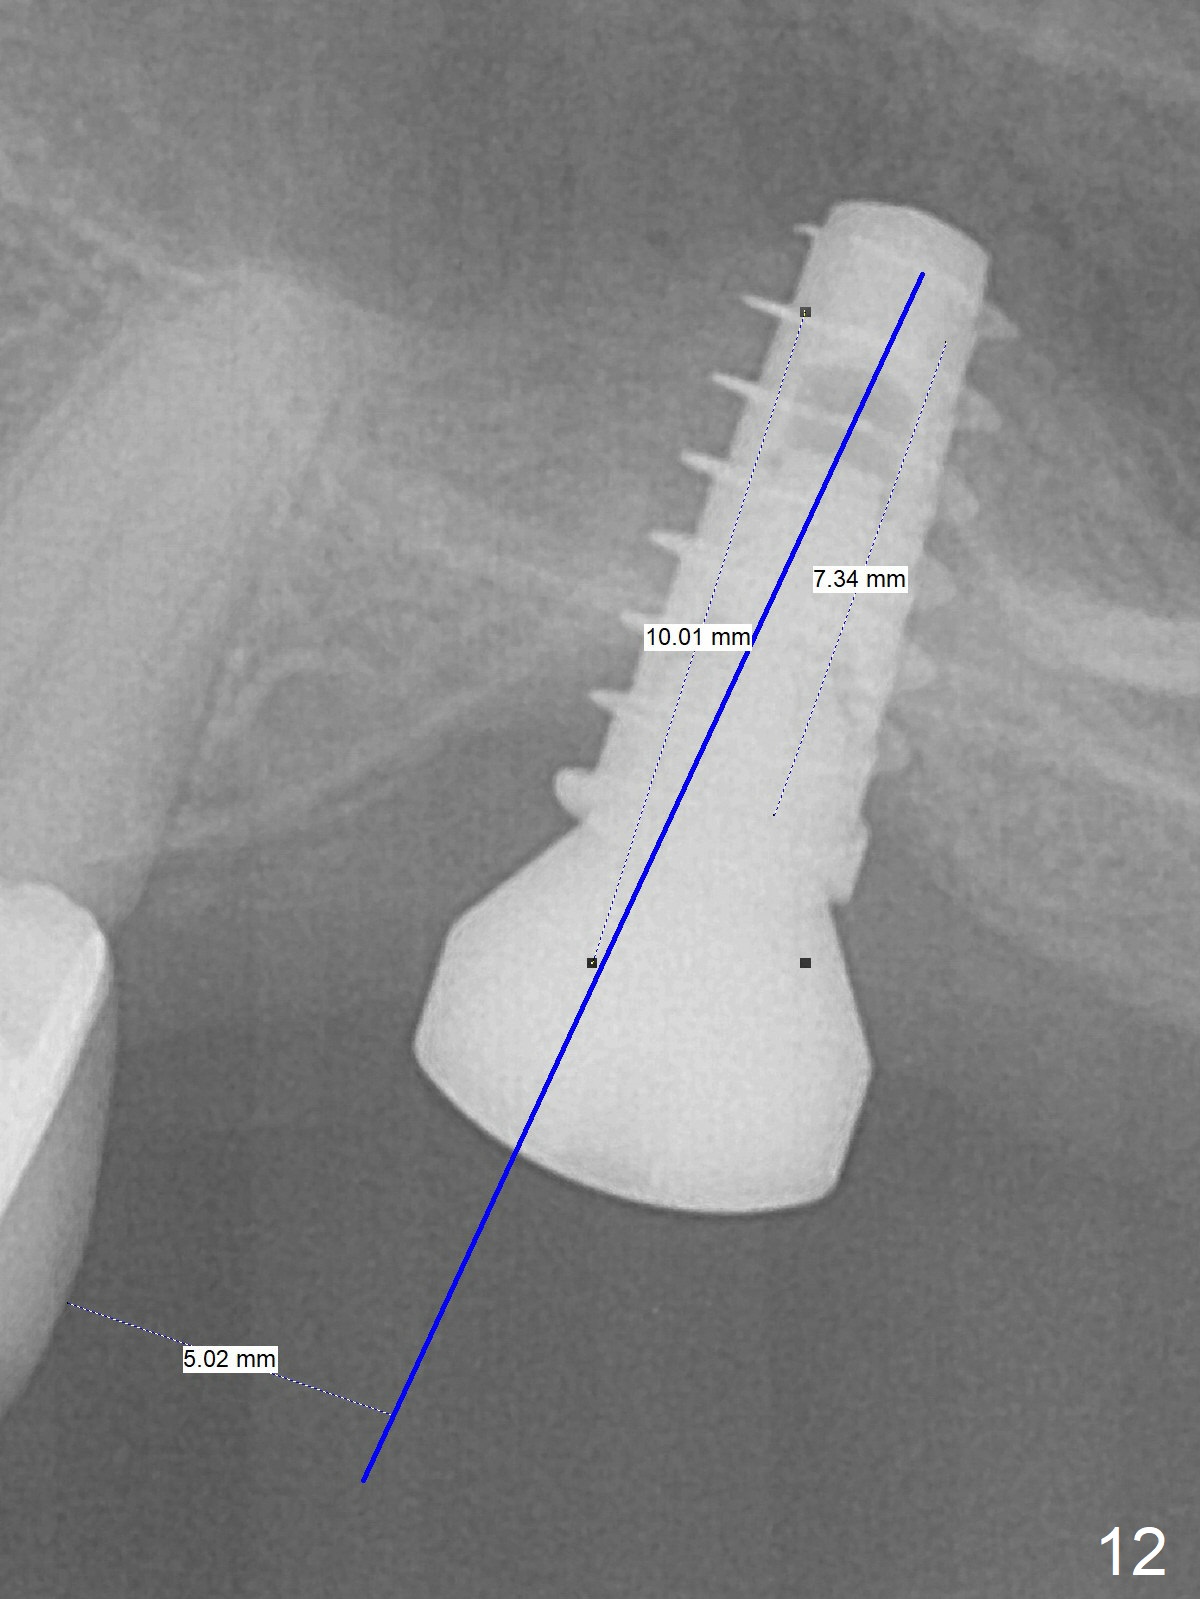

Three weeks later (approximately 8.5 months postop), the implant is found to be able to rotate when a 6.5x5.7(1) mm pair abutment is tightened with local anesthesia (there is pain associated with healing screw removal). After removal of the latter, the implant is placed deeper by hand retightening (Fig.10 arrow). Is it a better idea to use a new larger implant instead? The patient (53 years old) is scheduled to return for follow up in 3 months. In fact she returns 4 months later. The implant remains unstable and tender with loss of the crestal bone (Fig.11 *). It will be replaced with an implant (larger in diameter (5-6 mm), but shorter (7.3 mm after 5x10 mm dummy) with SLA surface after debridement and bone graft. Change the trajectory so that the coronal end will be more mesial (Fig.12 blue line). Use a healing screw and try to close the wound. In fact the patient reveals history of osteoporosis.